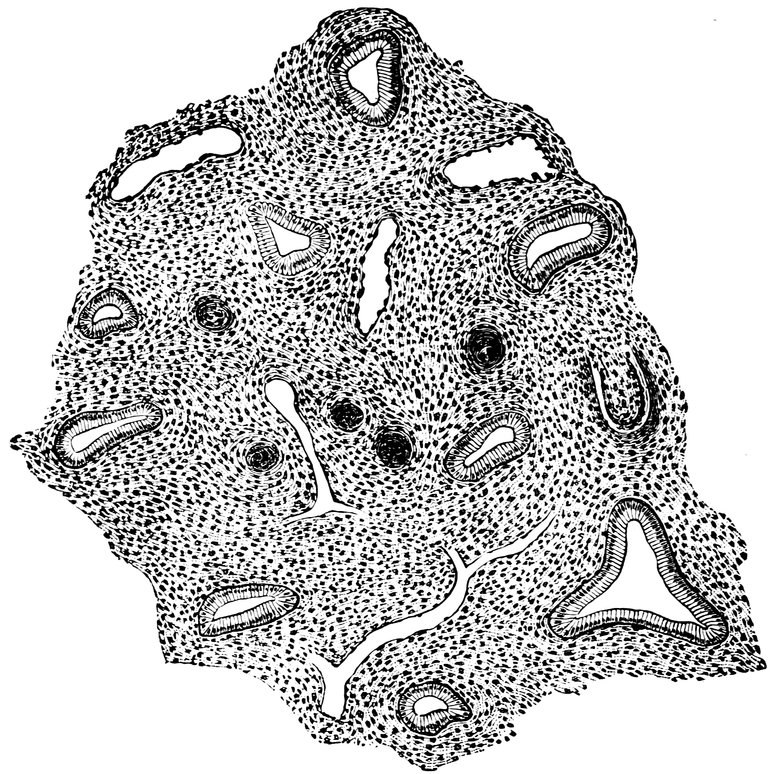

| 15. | Primitive follicles | 58 |

| 16. | Ripening follicles | 61 |

| 17. | Graafian follicles | 62 |